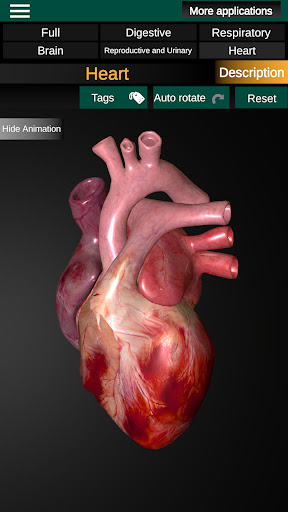

* Heart, which includes the atria, ventricles, aorta and an animation of this organ.